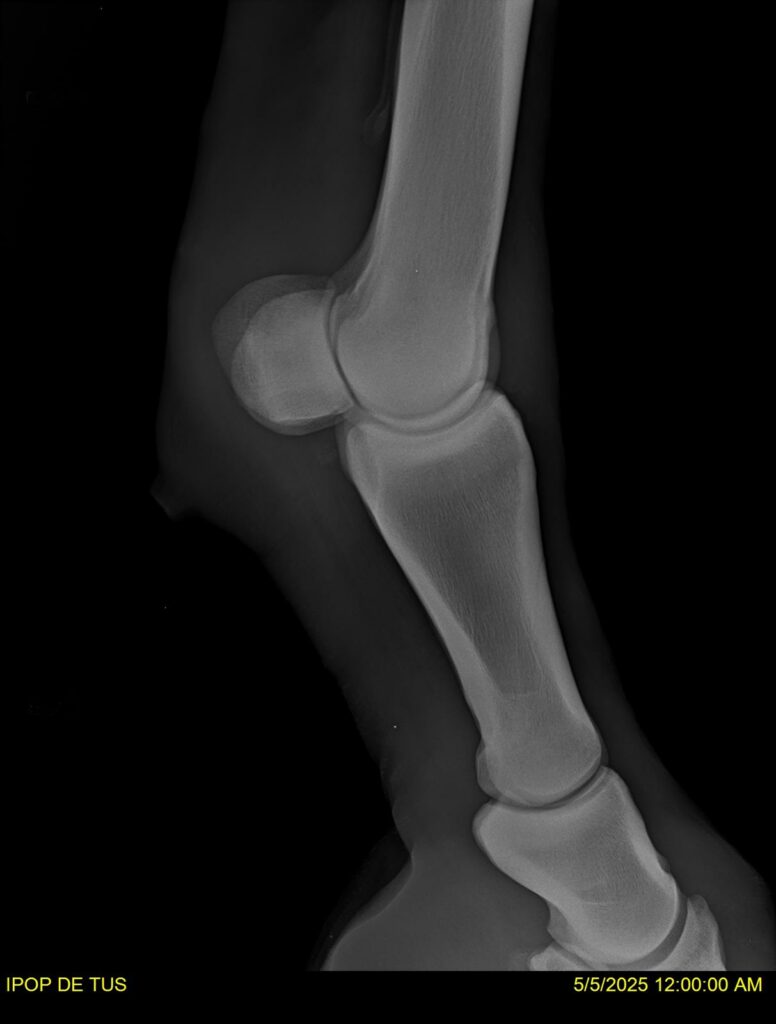

IPOP DE TUS, selle français, hongre, prendra 8 ans en 2026. LIFESTYLE x EROTICBLUS MONTOIS. Sans faute sur 125 et 130. Gentil cheval, respectueux avec des moyens et de la force. Transport OK, maréchalerie OK (pieds nus), santé RAS, Bilan clichés radios + clinique OK.

RADIOS ET CLINIQUE